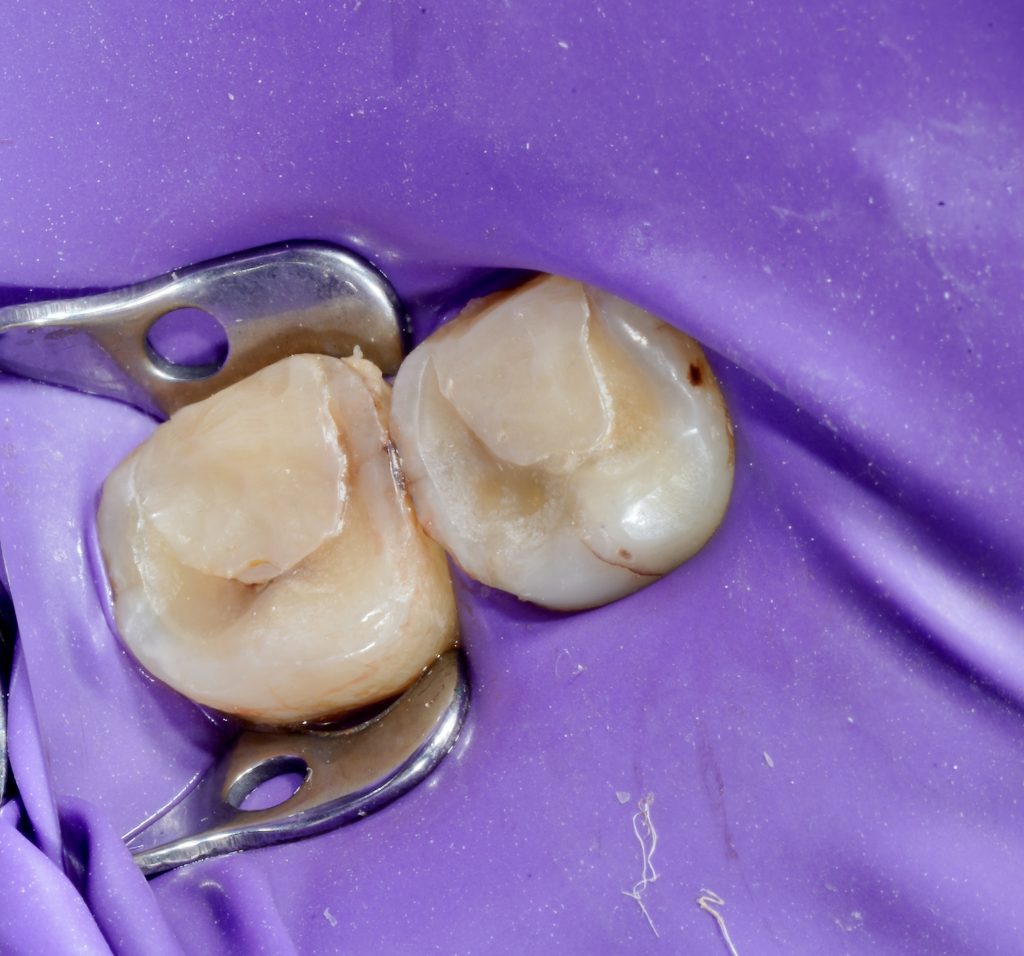

2️⃣ Isolation and Access Preparation

Rubber-dam isolation was achieved for both teeth using a single-quadrant clamp system (Fig 2). Conservative access cavities were prepared under a dental microscope. Caries and previous restorations were completely removed, revealing multiple canal orifices in each molar.